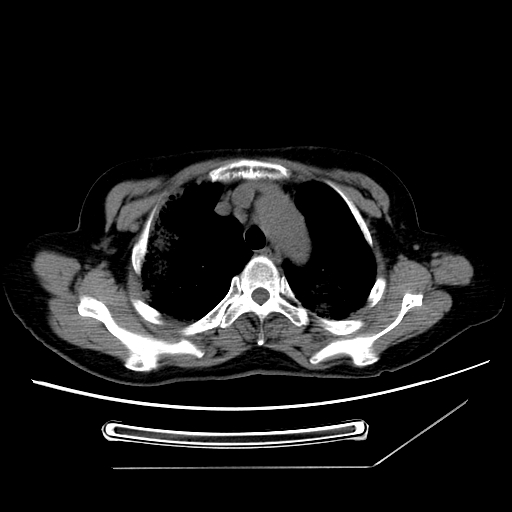

标题: CT25393:病人45岁,咳嗽,吐黄痰带血丝,发热,胸闷月余 [打印本页]

1、左肺中央型肺癌并双肺弥漫性转移   2、双肺部感染    3、肺大泡     4、左侧胸腔积液

双侧肺弥漫性病变,可见“空泡征”及“蜂窝征”,考虑肺泡癌可能性大,左侧胸腔积液,考虑胸膜受累可能!

1)不排除肺泡癌可能。2)左侧胸腔积液。